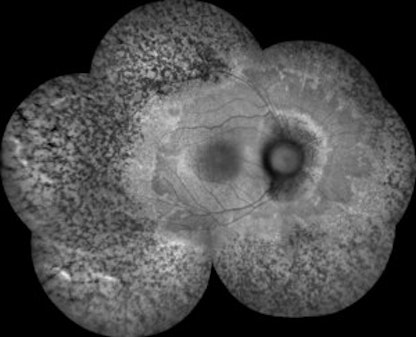

Intravitreal Injection of Allogeneic Human Retinal Progenitor Cells for Treatment of Retinitis Pigmentosa: Results from the Phase 2b Trial

• Retinitis Pigmentosa

• Retina

• cell therapy